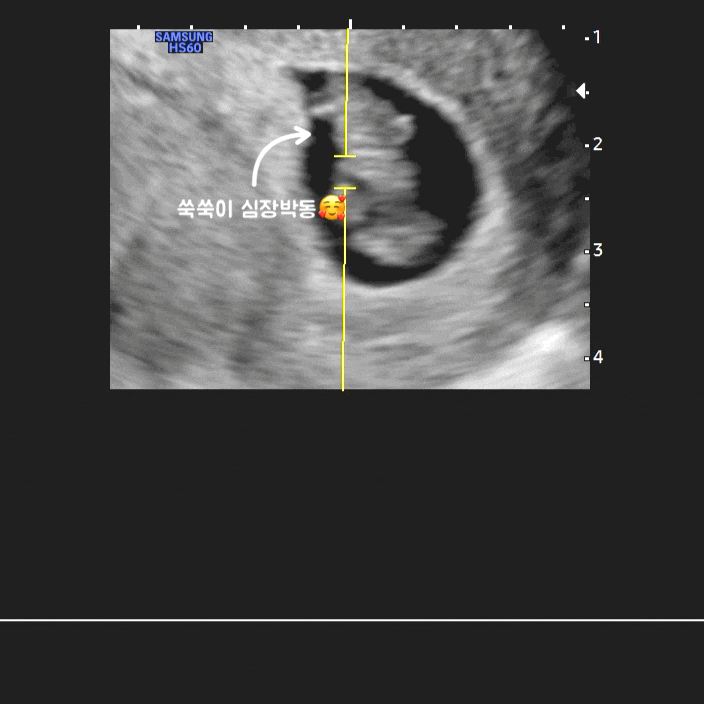

[임신일기/쑥쑥이 성장기록] 임신 7주차 증상, 심장소리 듣고 온 날의 기록?

2023. 06. 01 (목) 이식 후 일주일마다 가고 있는 #수지마리아 6월 1일 날짜로 딱 7주가 되던 날이었는데 ...